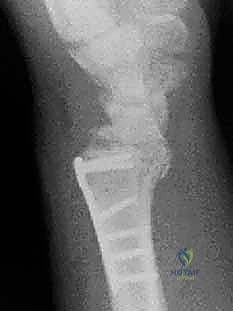

1. الأشعة السينية (X-rays): بوضعيات متعددة (أمامية خلفية، وجانبية دقيقة). الوضعية الجانبية الحقيقية (True Lateral) حاسمة لاكتشاف أي خلع جزئي في المفصل (DRUJ).

2. الأشعة المقطعية ثلاثية الأبعاد (3D CT Scan): تُستخدم في الكسور المفتتة أو كسور رأس الزند المفصلية المعقدة، حيث تعطي خريطة دقيقة للجراح قبل الدخول لغرفة العمليات.

ثانياً: العلاج الجراحي (Surgical Intervention)

خطوات التدخل الجراحي الدقيق مع الأستاذ الدكتور محمد هطيف

تُعد جراحات المعصم والزند من الجراحات الدقيقة التي تتطلب مهارة عالية، وهو المجال الذي يتفوق فيه الأستاذ الدكتور محمد هطيف بفضل استخدامه لتقنيات الجراحة المجهرية (Microsurgery) والأدوات الجراحية ذات التقنية العالية.

يقوم الدكتور هطيف بدراسة الأشعة المقطعية ثلاثية الأبعاد بدقة، ويختار نوع وحجم الصفائح المعدنية (Plates) والمسامير (Screws) المناسبة لكل مريض بناءً على حجم العظم ونوع الكسر.